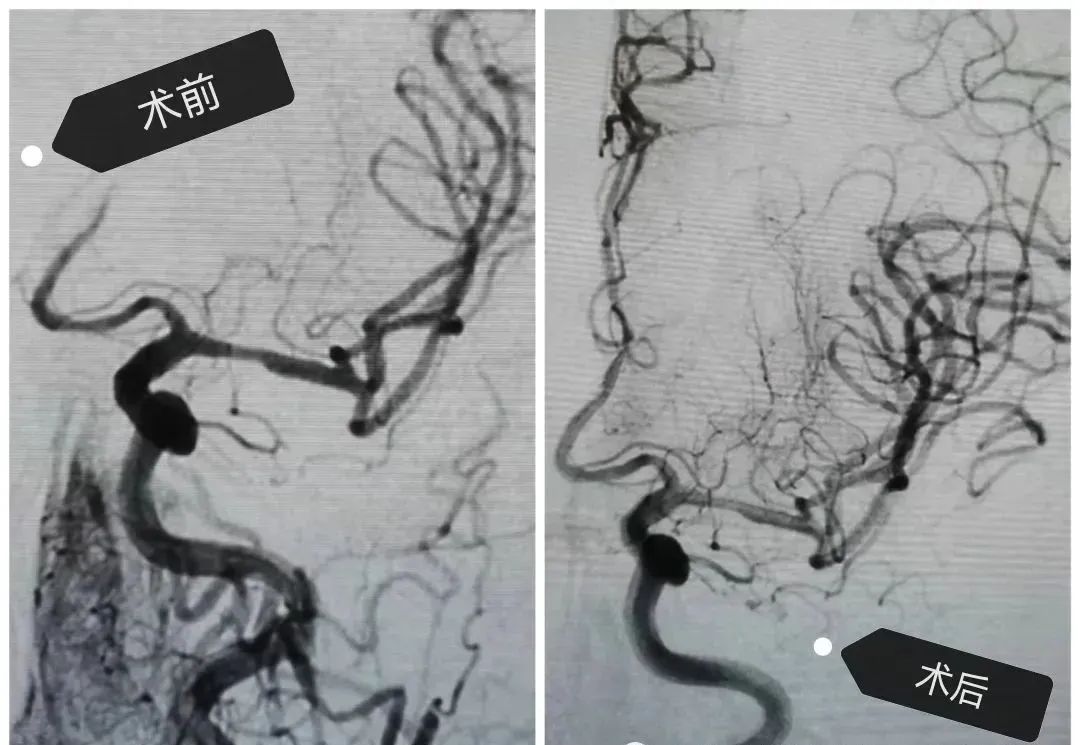

不幸的是溶栓2小時后,患者病情再次加重,出現(xiàn)不能說話,右側(cè)肢體全癱的病癥,考慮到再次梗塞的情況發(fā)生。卒中小組-神經(jīng)外科王芃主任緊急會診后建議全腦血管造影術(shù)(DSA)及介入治療,術(shù)中顯示患者左側(cè)大腦前動脈閉塞,需立即采取動脈內(nèi)開通技術(shù),再通大腦前動脈后幫助患者轉(zhuǎn)危為安。術(shù)后患者病情很快好轉(zhuǎn),語言和肢體功恢復,經(jīng)短期康復后出院。

腦血管造影(DSA)

《中國腦卒中防治指導規(guī)范2021版》指出,我國腦卒中發(fā)病率逐漸年上升,且呈年輕化趨勢,目前是我國第一位死亡原因和致殘率最高的疾病。由于腦組織的特性,腦卒中一旦發(fā)病,很快且不可逆,因此時間就是生命,時間就是大腦,超早期治療是降低死亡率,減少致殘率最佳方法,腦血管造影是目前腦卒中病因診斷的金標準,介入治療創(chuàng)傷小,操作便捷,療效可靠,預后好。